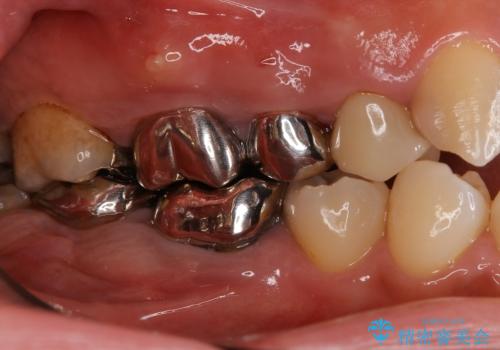

- 奥歯で噛んだ時の違和感を主訴に来院された患者様です。

歯根の先端の病変が大きく割れてしまっていた為、抜歯の必要がありました。

レントゲン等、検査を行ったところ骨の厚みは問題ないですが、

高さは少し低かったので、幅が太い短いインプラントを使って治療を行う計画を立てました。